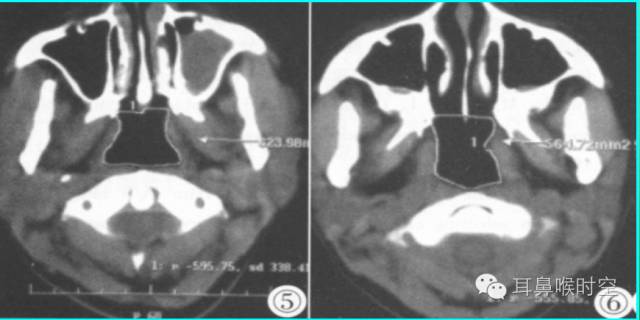

图1 鼻咽气腔N值 图2 腺样体A值

③同层动态CINE:

利用GE公司HispeedAW工作站,选择任意3个层面测量(图3,4)

求两两之间的面积最大差值(△S=118.04- 91.15) 。

图3 鼻咽气腔有效面积 Sn 图4 CINE测量有效面积 Sn1

标准CT 轴位像:

鼻咽气腔形态因层面不同而不同,其中,呈梯形(图3),长方形(图4)。

咽隐窝及咽鼓管咽口清晰或隐约可见,双侧对称,鼻后孔大部分畅通,咽旁间隙清晰,邻近骨质无破坏。